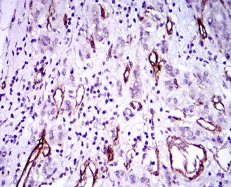

IHC    1/200 - 1/1000